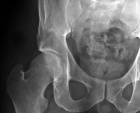

37 year old male presents with discomfort of right gluteal region surgical site, and increasing numbness and tingling over dorsum of right foot

Zoom image: Radiological image Radiological image.